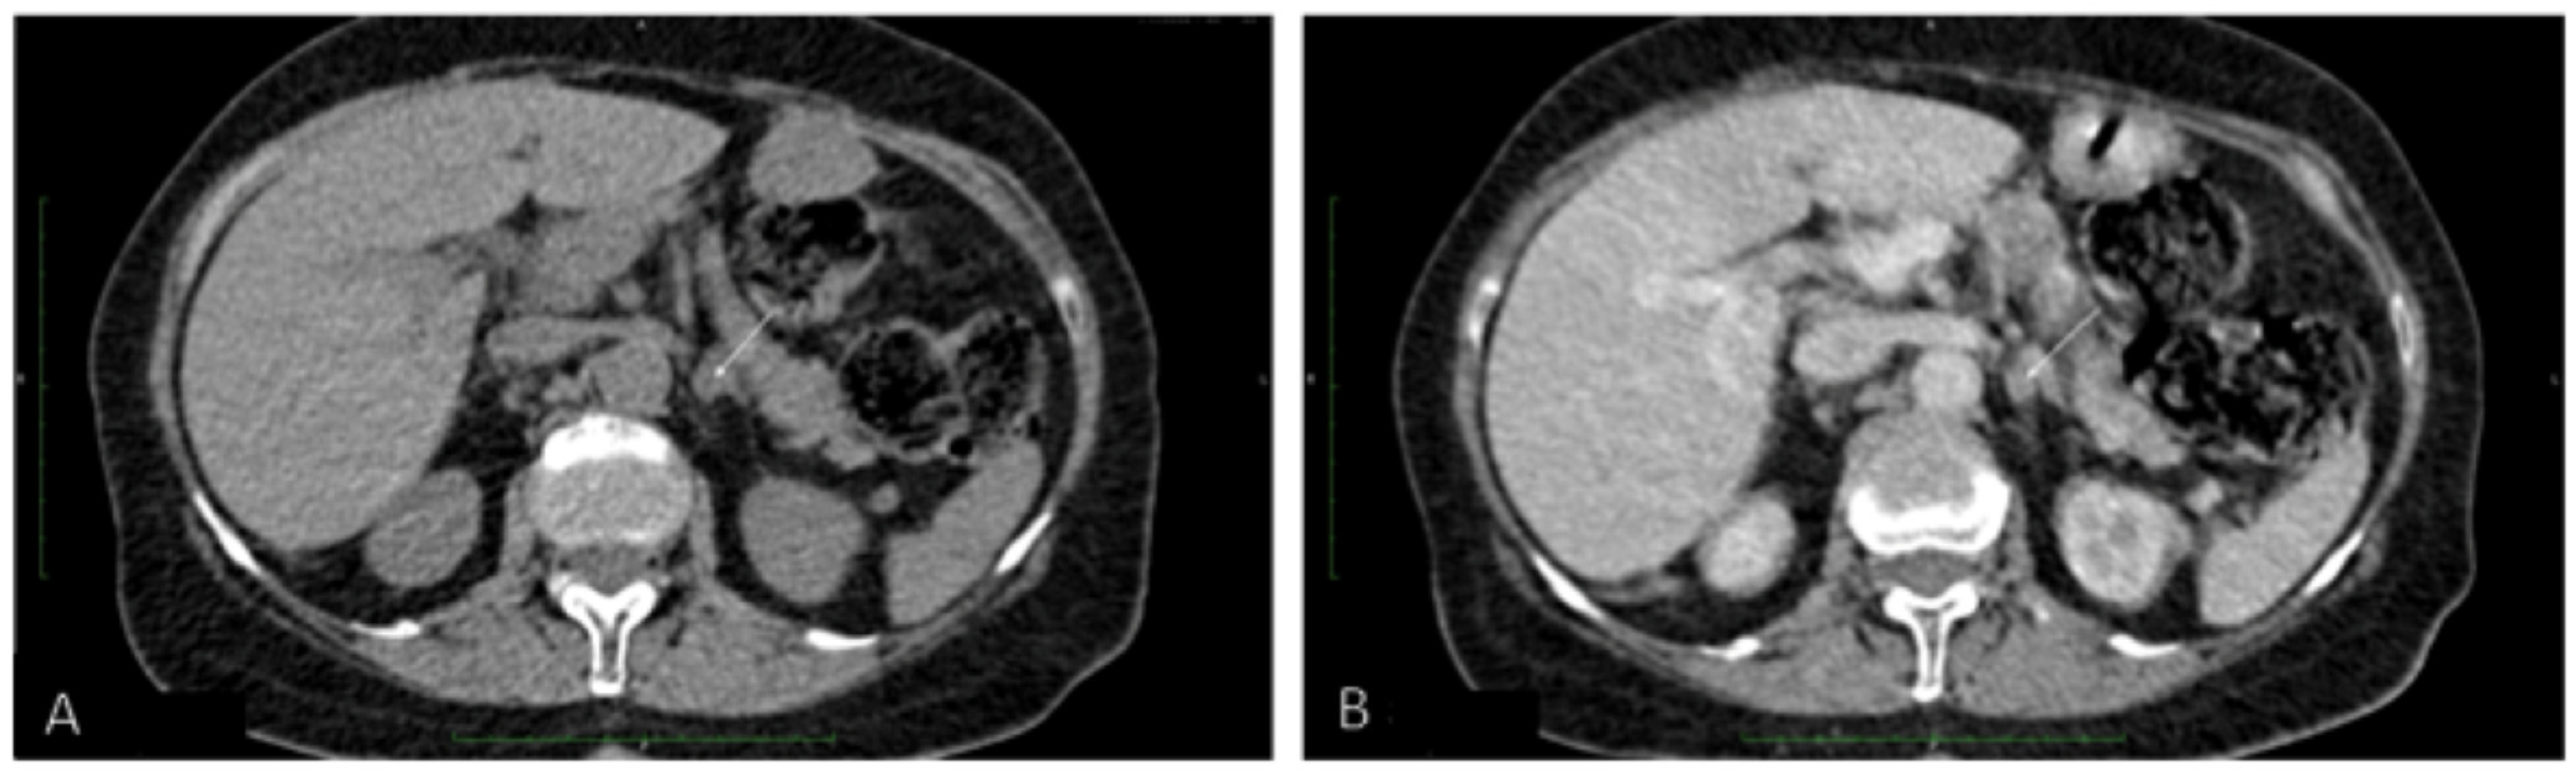

Because PHEO was suspected, the 24 h urinary test was repeated, showing normal concentrations of metanephrine. Ultrasound (US) of the thyroid gland revealed two solid hypoechogenic lesions in the upper part of the right lobe, the first one measuring 35 × 29 × 41 mm with macrocalcifications, and the second measuring 22 mm in maximum diameter without calcifications. US also showed a hypoechogenic lesion, measuring 9 × 7 × 9 mm, in the left lobe (Figure 2), but no lymph nodes suggesting regional metastases. A risk of malignancy of each thyroid nodules was estimated according to the EU-TIRADS classification system [13]. A chest X-ray was normal, whereas abdominal computed tomography (CT) revealed a focal lesion, measuring 12 × 9 × 13 mm, in the left adrenal gland, with non-contrast and contrast-enhanced attenuation levels of 24 and 78 Hounsfield units, respectively (Figure 3).

Because CT imaging did not result in a clear exclusion of PHEO, magnetic resonance imaging (MRI) with contrast enhancement was performed, showing segmental thickening of the medial branch of the left adrenal gland and a solid focal lesion, measuring 11 × 9 mm and with well-defined edges, indicative of a low-fat adenoma without any characteristics of PHEO, so additional procedure such as scintigraphy with metaiodobenzylguanidine (MIBG) was not performed. MRI did not reveal any other significant lesions in the abdomen, including the liver. Fine-needle aspiration (FNA) biopsies of the larger nodule of the right thyroid lobe (Figure 2A) and the focus of the left thyroid lobe (Figure 2C) revealed bilateral MTC (Figure 4A). To confirm the diagnosis of MTC, Ctn concentrations were measured in both FNA washout fluids, but Ctn was significantly higher than normal only in the specimen retrieved from the right lobe (15,417.00 pg/mL).

Figure 3. Abdominal computed tomography (A) without and (B) with contrast of a focal lesion in the left adrenal gland.